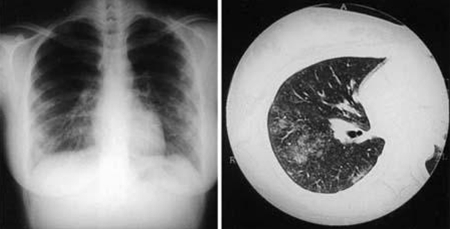

Coxiella burnetii pneumonia. CXR and CT scan from a 21-year-old woman with Coxiella burnetii pneumonia; CXR shows multiple areas of soft consolidation in the middle-to-lower lung fields bilaterally; CT scan shows poorly defined centrilobular nodules and air space consolidation

Okimoto N, et al. Respirology. 2004;9:278-282; used with permission of John Wiley & Sons Ltd